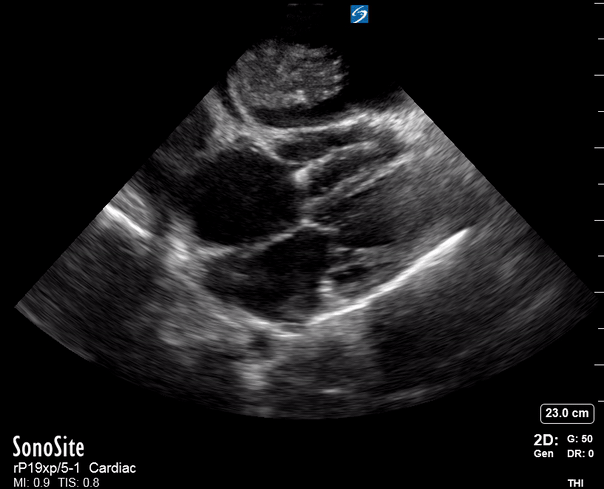

Exit: is there acute aortic root pathology?

Thoracic Aortic dissection is a time-dependent and deadly pathology that can occur silently or be masked by a variety of clinical presentations. While angio-CT remains the gold standard for diagnosis, US may be performed quicker and at the bedside. In the visible portion of the aortic root, the US findings can include intimal flap, aortic valve insufficiency, retrograde aortic flow, or rupture into the pericardium with pericardial effusion and tamponade. Alternatively, dilation of the aortic root is characteristic of a thoracic aortic aneurysm.

Importantly, remember that thoracic aortic dilation or intimal flap may occur distal to the aortic root, where an US scan is usually blind. Hence, the absence of dilation or flap does not rule out aortic disease.

THE VIEWS

The PLAX view is best for exploring the aortic root. If performed by an experienced operator, aortic root measurements in this window correlate well with angio-CT measurements.

The Aortic root size varies with age and gender and should be measured at its widest point, perpendicular to its long axis. In general, a root > 4 cm should be considered borderline and enough to warrant a formal study.

Alternatively, the aortic root size can be estimated by the rule of thirds, where in the PLAx view the size of the RV, AoR, and LA should be roughly 1:1:1.

AORTIC DISSECTION

In both of these views, US may detect an intimal flap seen as a hyperechoic linear structure within the aortic lumen that moves with each heartbeat. The visualization of a flap carries a high specificity and should prompt immediate consultation with cardiothoracic surgery; however, ultrasound sensitivity for intimal flap is significantly low, and its absence does not rule out aortic dissection.